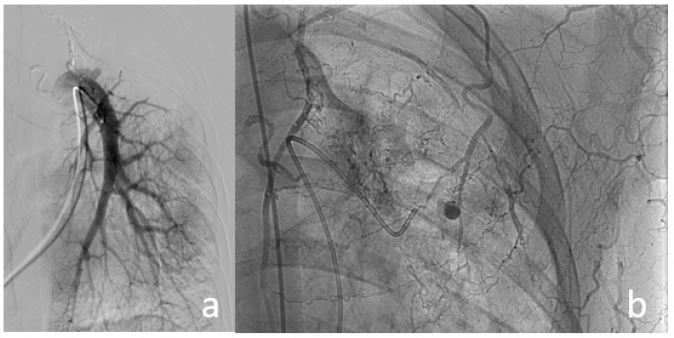

Figure 2: (A) Pseudoaneurysm visualized on selective angiography of the left internal mammary artery, followed by selective embolization using glue. (B) Post-procedural image after the first intervention shows the pseudoaneurysm with reduced contrast enhancement compared to baseline.

Figure 3: (A) Digital Subtraction Angiography (DSA) of the pulmonary artery shows absence of several left pulmonary arterial branches due to increased vascular resistance from underlying pulmonary damage and reversed blood flow. Selective catheterization of the pseudoaneurysm via the pulmonary artery failed due to the small and inaccessible feeding branch. (B) Attempted direct puncture using an 18G needle under DSA guidance was unsuccessful. The patient experienced 50 mL of hemoptysis, which was managed locally, resulting in temporary hemostasis.